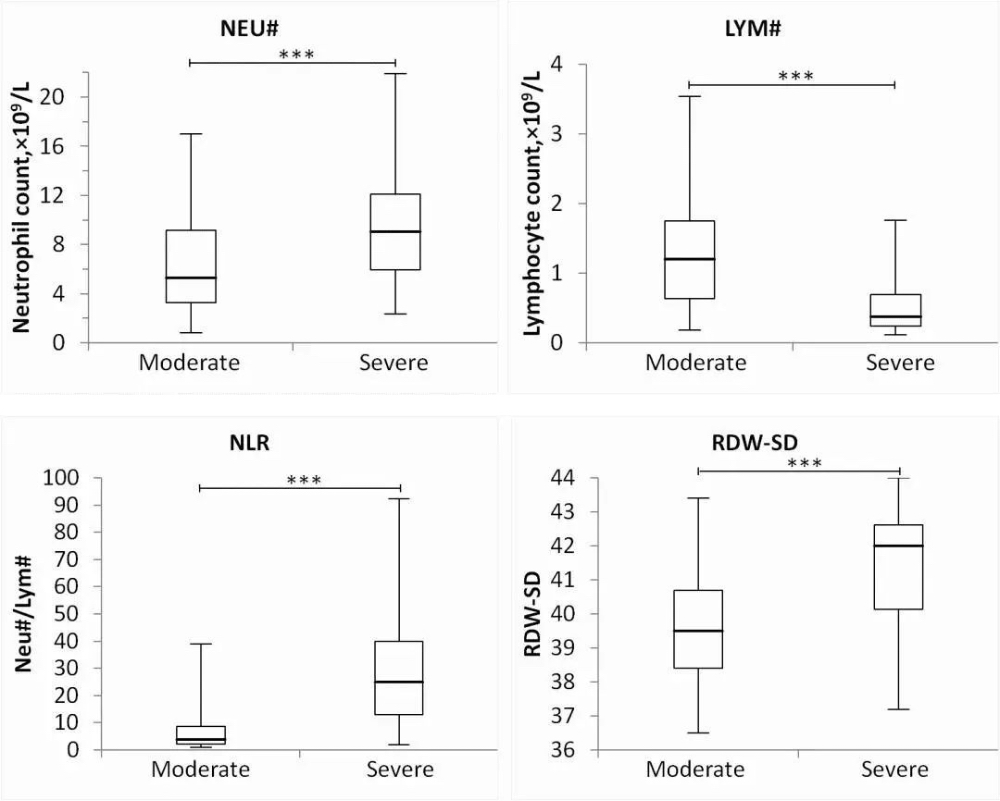

A. From the comparison between CBC tests from moderate and severe cases, it could be concluded that, as the patientвАЩs condition deteriorates, his or her:

*** indicates that p<0.001